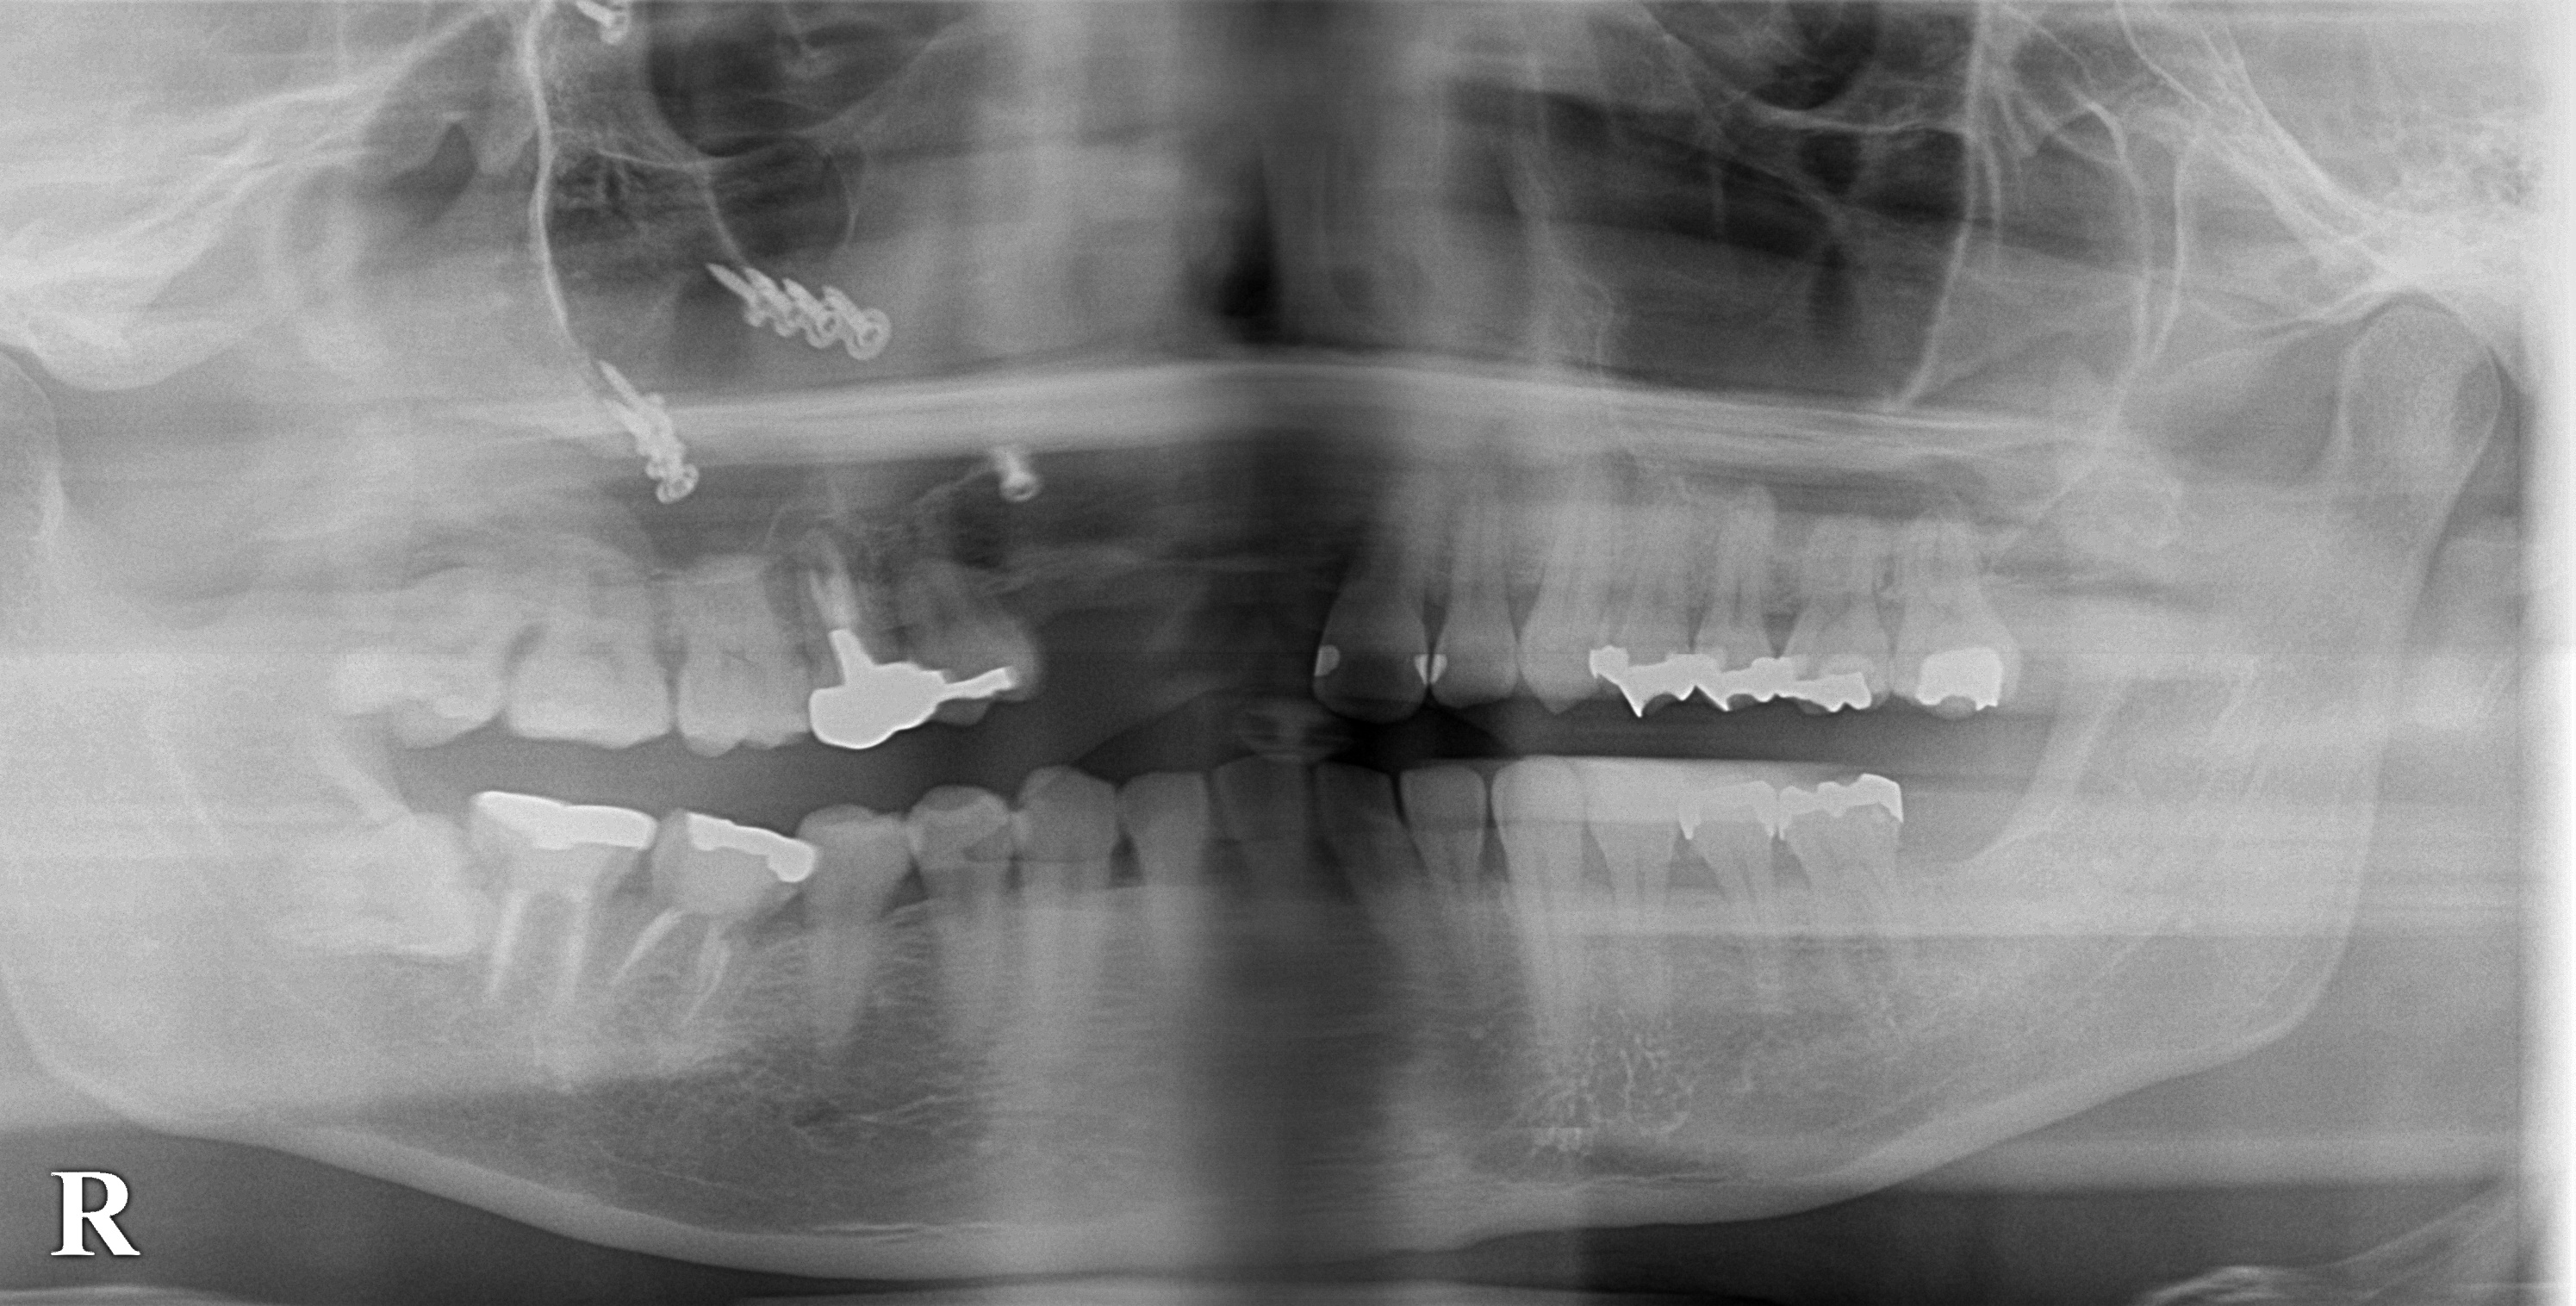

レントゲン写真を見ると、骨折の手術で使用したプレートとスクリューを認めます(上段の写真)。

CTを撮影してみると、歯を失ったと同時に歯を支える骨も失われていて、インプラントを埋入するには骨の厚みが不足していました(2段目左の写真)。

そこで、本日、インプラント埋入と同時に、骨の厚みを増生する手術を加えて、3歯の欠損に対して2本のインプラント埋入術を行ないました。

2段目右の写真が手術後のCTで、インプラントの外側に骨補填材が白く写っています。